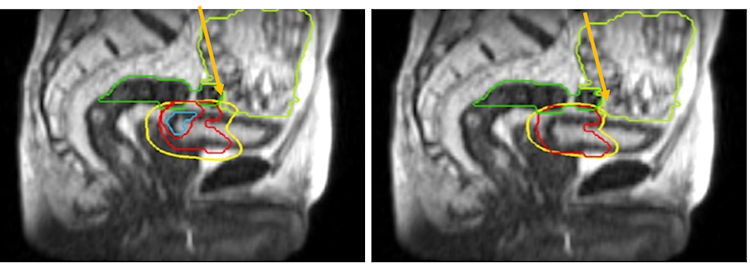

MRI装置と放射線治療装置が一体化したMRIdian(メリディアン:ViewRay社)は、現在日本で当院を含めた2施設に導入されています。

MR画像を用いて事前に治療計画を行いますが、治療直前や治療中にリアルタイムのMR画像を取得することができます。CTよりも軟部組織の分解能が高く、被ばくしないことが特徴です。さらに治療直前の画像に線量分布を重ね合わせ、腫瘍や周囲リスク臓器のその日の投与線量を確認することができます。

線量分布が好ましくない場合、その日の最適な線量分布にするべくその場で再治療計画を行うことも可能です(On-line Adaptive RadioTherapy)。

既存の装置でも再治療計画を行うことはできましたが、少なくとも翌日以降の治療に反映されることしかできませんでした(Off-line ART)。 MRIdianでは、日々変化する臓器において、治療のたびにリスク臓器の線量を守りつつ、ターゲットへの線量を増加することも可能となります。今まで根治が難しかった臓器での放射線治療成績の向上が期待されています。